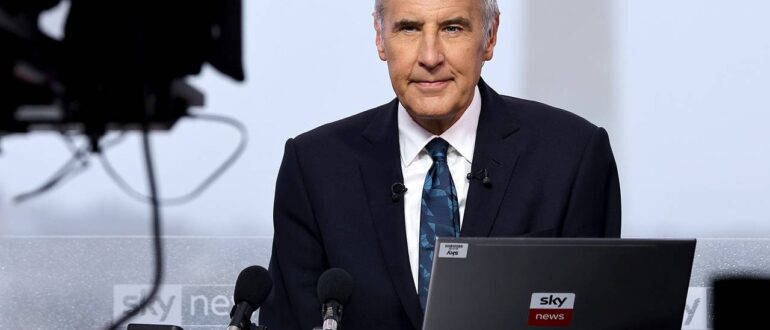

Известный британский телеведущий и журналист Дермот Мернаган, который борется с раком простаты на последней стадии, обратился к зрителям с просьбой не игнорировать, казалось бы, безобидный симптом. Эти слова…